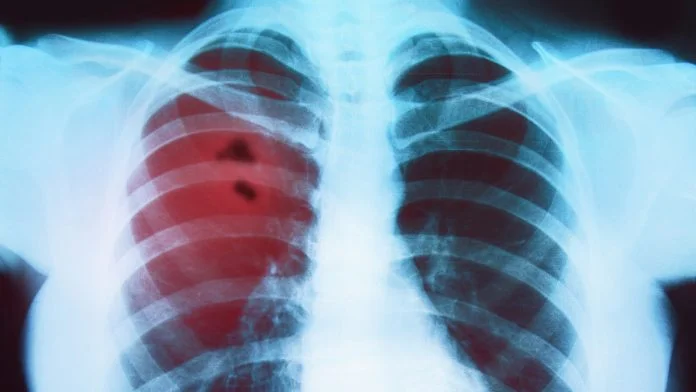

Depending on the patient’s type, location, and stage of lung cancer, lung surgery may be an option. To cure lung cancer with surgery, the tumor must be removed along with some surrounding lung tissue, as well as lymph nodes in the region of the tumor. In cases where the lung cancer is localized and unlikely to have spread, removing the tumor is considered the best option. This includes early-stage non-small cell lung cancers and carcinoid tumors. Lung cancer surgery can involve removing a portion of the lung or the entire lung.

The type of lung surgery you need for lung cancer depends on the size of the cancer, position in the lung, type of cancer (small cell or non-small cell), and whether it has spread.